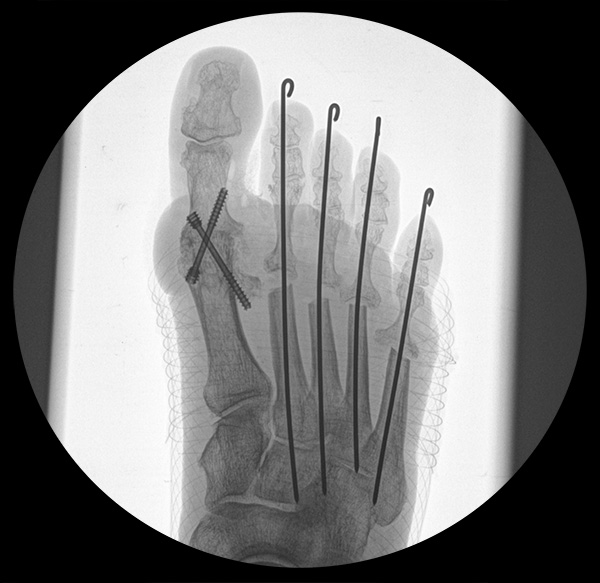

Deutlich bessere Ergebnisse wurden erreicht durch eine Kombination der OP nach Tillmann mit einer Arthrodese des Großzehengrundgelenks oder auch einer Lapidus-Arthrodese 611. Dies wurde bereits 1956 durch Vainio empfohlen, hat sich aber erst in diesem Jahrtausend flächendeckend durchgesetzt 121314.

Abschließend erfolgt die temporäre K-Daht Fixation sämtlicher Kleinzehen in achsgerechter Stellung. Die Strecksehnen werden in Verlängerung vernäht.